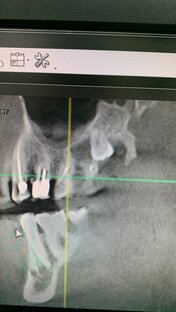

«Я сам себе назначил КТ»,- с этих слов начинается консультация немолодого пациента. И сразу как-то понятно, что это «Хлестаков на базаре», он ходит пробует, но не покупает. Этот всезнающий пациент не даёт сказать или закончить мысль. И внутри зарождается ощущение, что нам с ним не по пути. И в подтверждение этого ощущения звучит следующий вопрос : «Может нижний спасём? Мне в другой клинике предложили спасти». Имеется ввиду нижний полностью разрушенный зуб. И внимательно-оценивающий взгляд! Всё пазл сложился, точно не по пути. С этим конкретным пациентом будет так : если всё пойдёт и хорошо - то это он молодец, но не дай бог произойдёт какая-то внештатная ситуация все громы-молнии падут на голову врача. Так что очень мягко и аккуратно объясняю, что план лечения составляет только врач, а уж лечиться или нет, решает пациент. И тут же получаю : « Да знаю я вас, здоровые зубы лечите и удаляете лишь бы денег срубить»,- встаёт с кресла и исчезает в дали! И ему не жалко своего времени? И этот товарищ найдёт «специалиста» который ему «спасёт» зуб и через короткое время этот зуб его покинет, но как говорится эту историю буду писать уже не я.